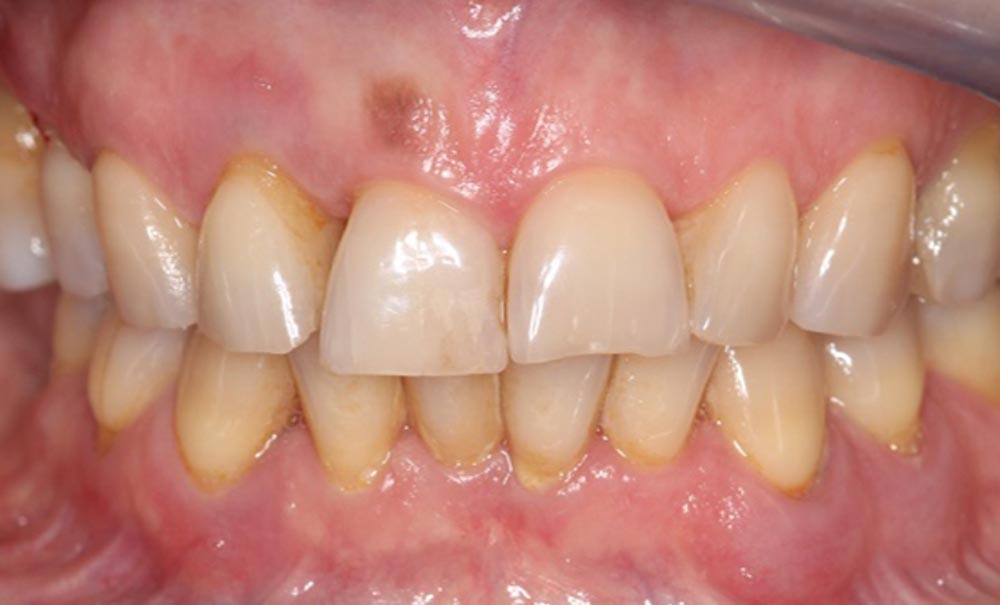

Qu’est-ce qu’une parodontite stade IV grade B selon Chicago 2017 ?

Il s’agit d’une parodontite sévère à progression modérée avec perte potentielle de toute la denture [1].

Le stade IV est caractérisé par :

- une perte d’attache clinique (CAL)* interdentaire (dans le site le plus atteint et sur au moins 2 dents non adjacentes) ≥ 5 mm ;

- une perte osseuse radiographique** s’étendant jusqu’au tiers moyen ou apical de la racine ;

- un nombre de dents perdues pour raison parodontale ≥ 5 ;

- une profondeur de poche ≥ 6 mm ;

- une alvéolyse verticale ≥ 3 mm ;

- la présence de lésions…